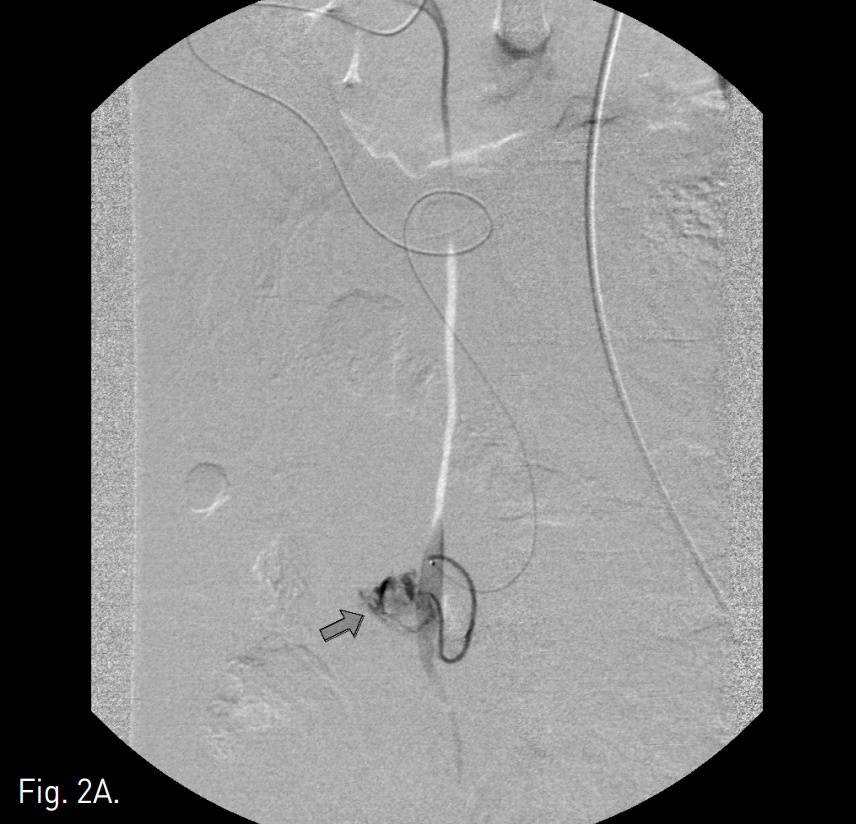

Fig. 2

A. A microcatheter was advanced into the distal portion of the bleeding omental artery (arrow).